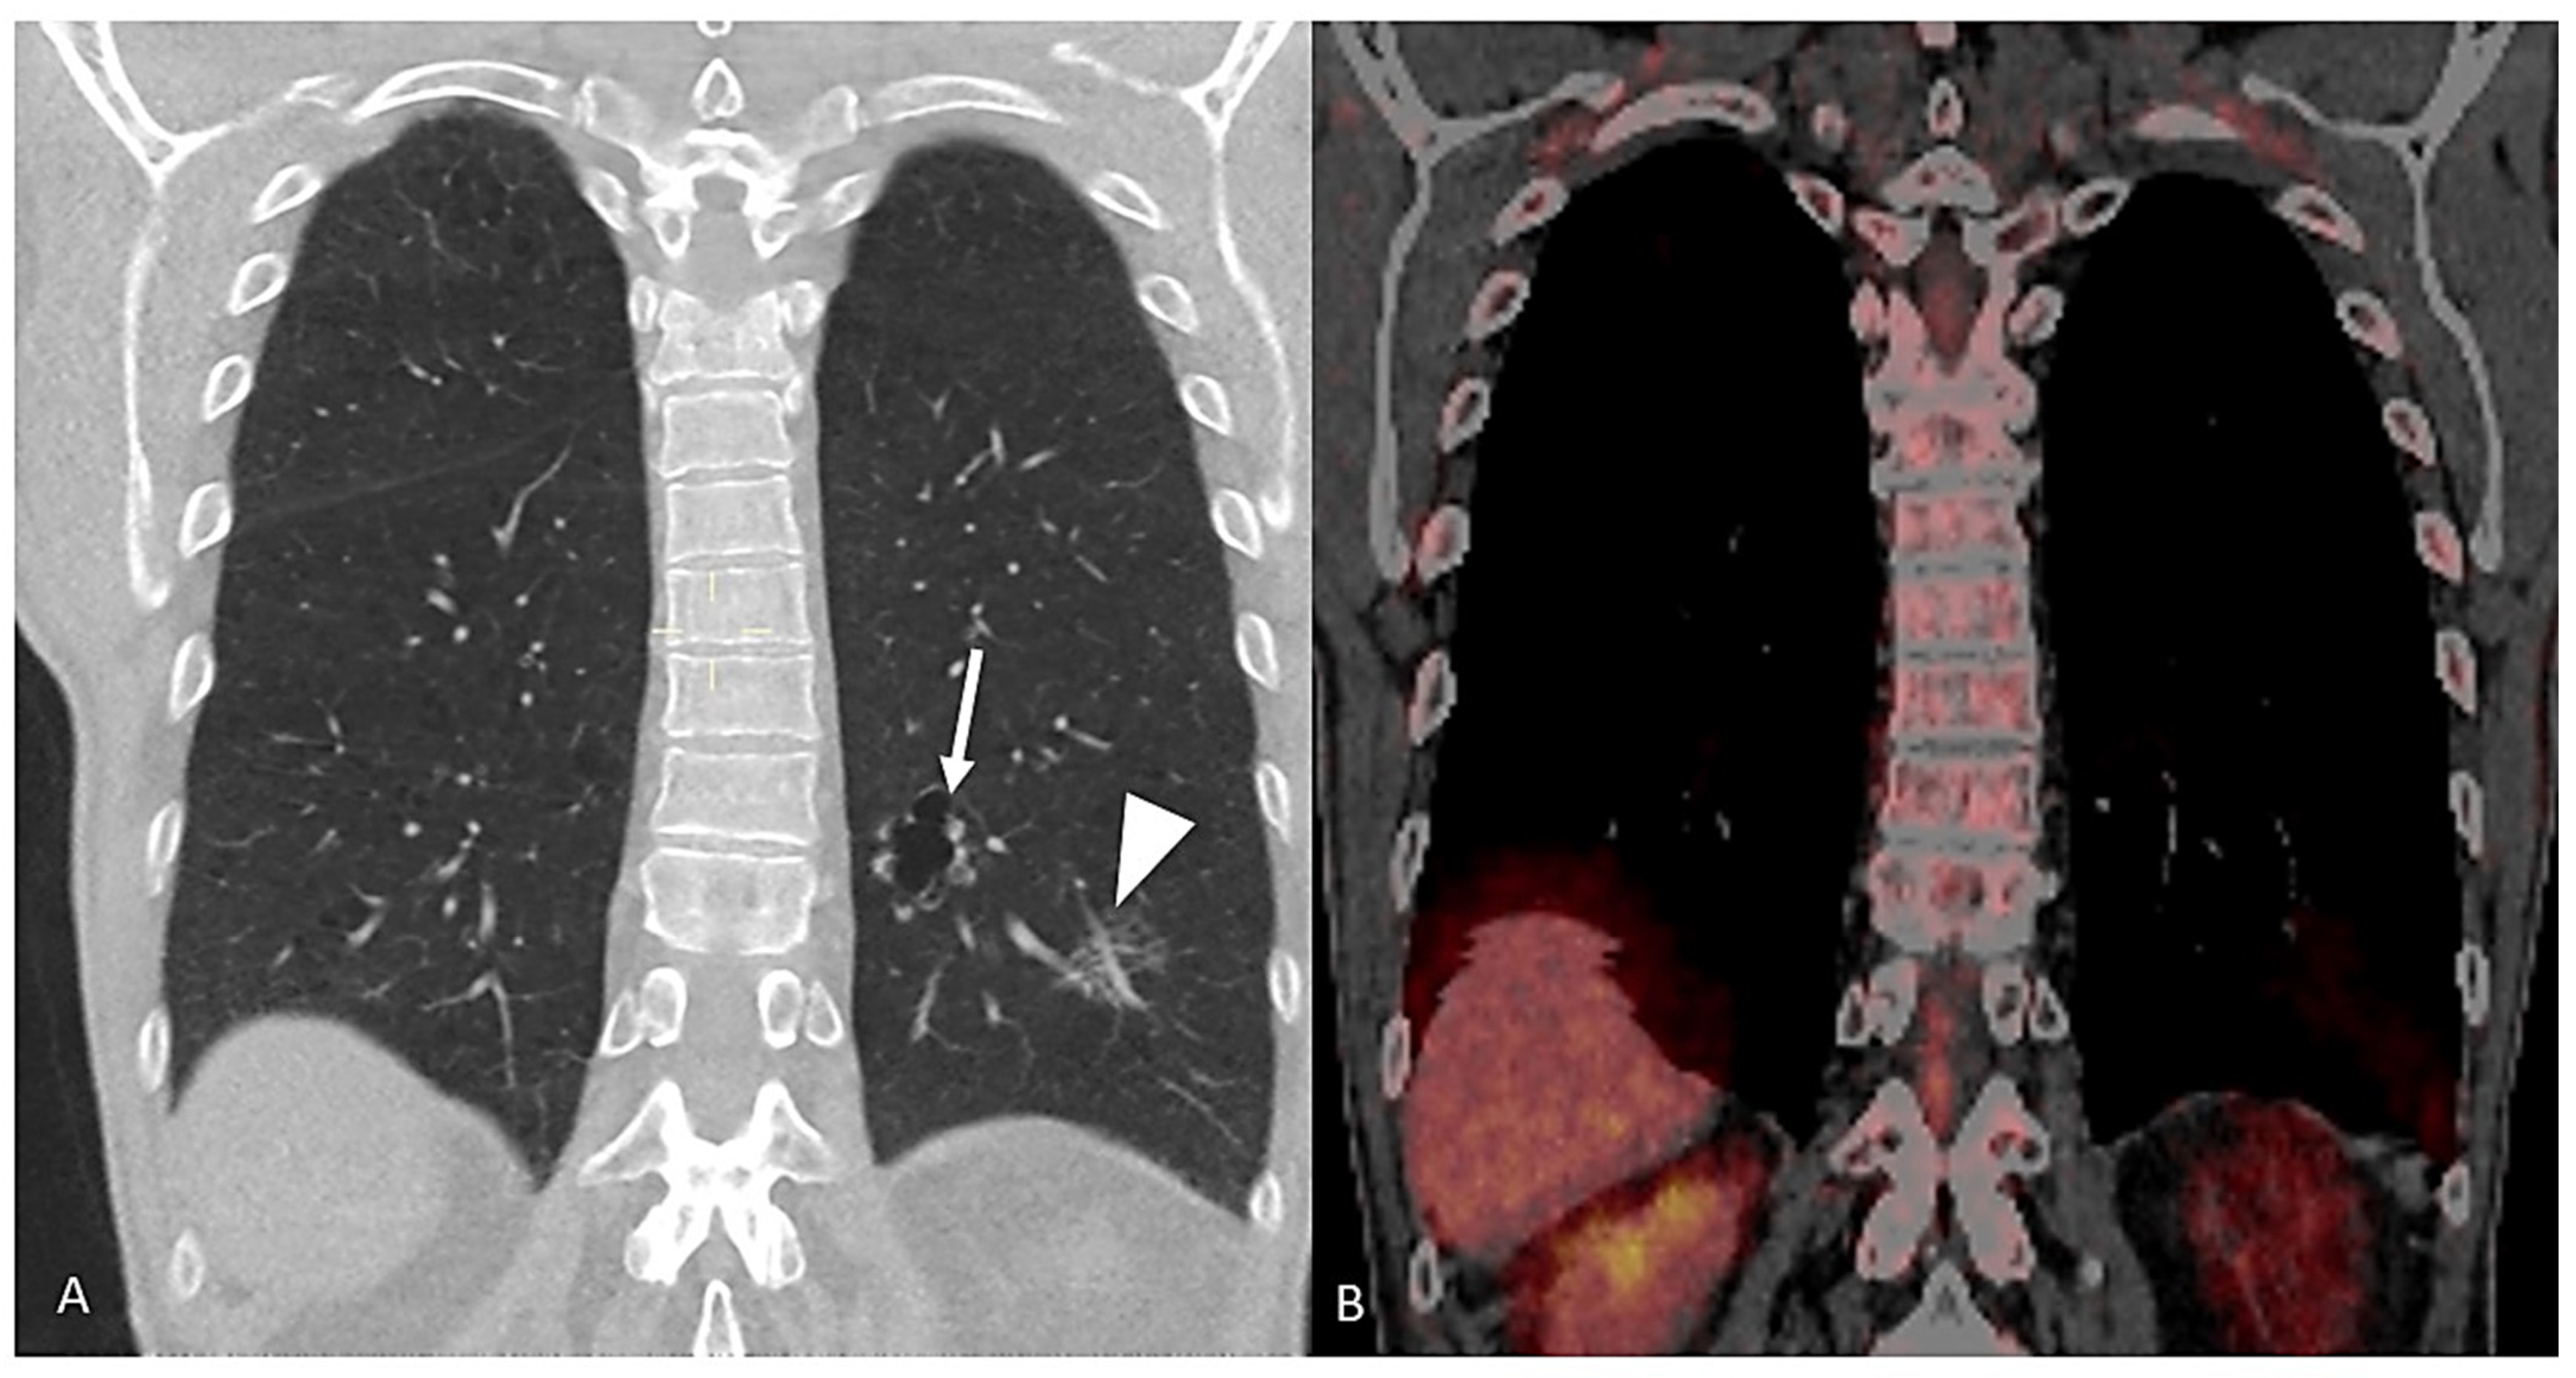

4.1. Positron Emission Tomography–Computed Tomography (PET-CT)